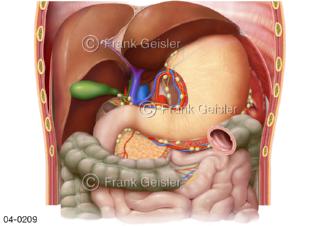

Bildergalerie Topografie Organe

Bilder zur topografischen Anatomie, die Lage der Organe und die Strukturen nach ihren räumlichen Lagebeziehungen zueinander, Übersicht der inneren Organe im Kopf und im Rumpf, Topografie der Organe im Brustraum (Thorax) und im Bauchraum (Abdomen)